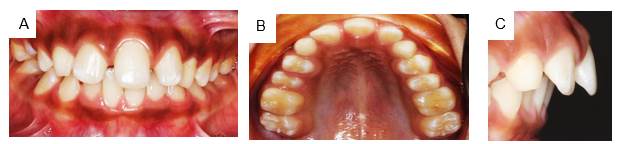

Male patient, 10 years old, weighs 23 kg, height is 123 cm, from Jamundí, Valle del Cauca, Colombia. He attended the office with his aunt, the adult in charge, who stated the following reason for consultation: “My nephew has only one front tooth”. During the interview, she explains that the child is the second of three term pregnancies. Family history: paternal aunt has diabetes, hypertension, and unspecified cancer. The child’s history is not reported. The aunt said the child’s deciduous dentition included only one upper central incisor. She also noted that his other two siblings have the same problem. The extraoral examination showed that the midline does not coincide with the tip of the nose nor the center of the chin; there is no labial philtrum, and the bipupillary plane is not parallel to the commissural line. There is lip incompetence, ears of increased size, projection, and implantation. (Figure 1) The intraoral examination showed a solitary central incisor on the maxillary midline, absence of labial frenulum and incisive papilla, an oval palate, and class II malocclusion with proinclination of the central incisor. (Figure 2 a, b, and c).

A. Front view showing the solitary maxillary incisor and deep bite. B. Occlusal view showing absence of interincisive papilla. C. Lateral view showing mandibular retrognathism.